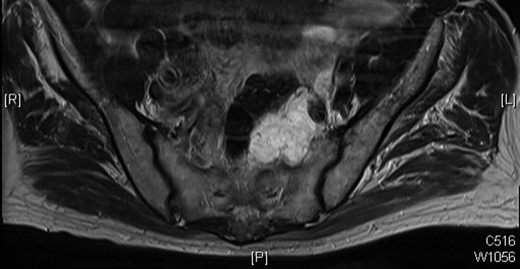

In October 2009, a magnetic resonance imaging (MRI) scan of his spine was arranged due to leg pain thought to be of neurological origin. This did, indeed, showed marked L5 and S1 spinal stenosis; however, it also showed an irregular mass in the left side of the pelvis anterior to the sacrum and abutting the distal rectum and the emerging left S1 nerve root on the anterior surface of the sacrum. Overall, the dimensions were 3.6 × 4.3 × 3.8 cm. There was a similar area of soft tissue on the previous CT of September 2008. The possibility of a further slow-growing rectal recurrence was raised. This was discussed at multidisciplinary team meeting and as the mass was cold on PET scan in March 2009, it was decided to repeat the PET scan, which was done in February 2010 and November 2010, and the mass again showed no uptake.

MRI scan of 2009 showing a mucinous mass in the left side of the pelvis below the anastomosis from his original sigmoid colectomy.